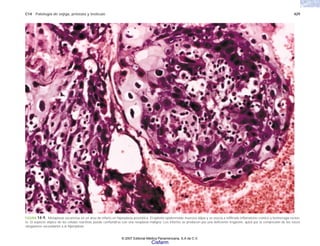

FIGURA 5-13. Glomerulonefritis en el lupus eritematoso diseminado. a) Glomérulo con

engrosamientos focales hialinos de la pared capilar (“asa de alambre”) y proliferación

focal de células mesangioendoteliales. b) Depósito de C en la pared de las asas capilares

glomerulares. c) Electromicrografía de parte de una asa capilar glomerular, con depósito de

complejos inmunes en el seno de la membrana basal.